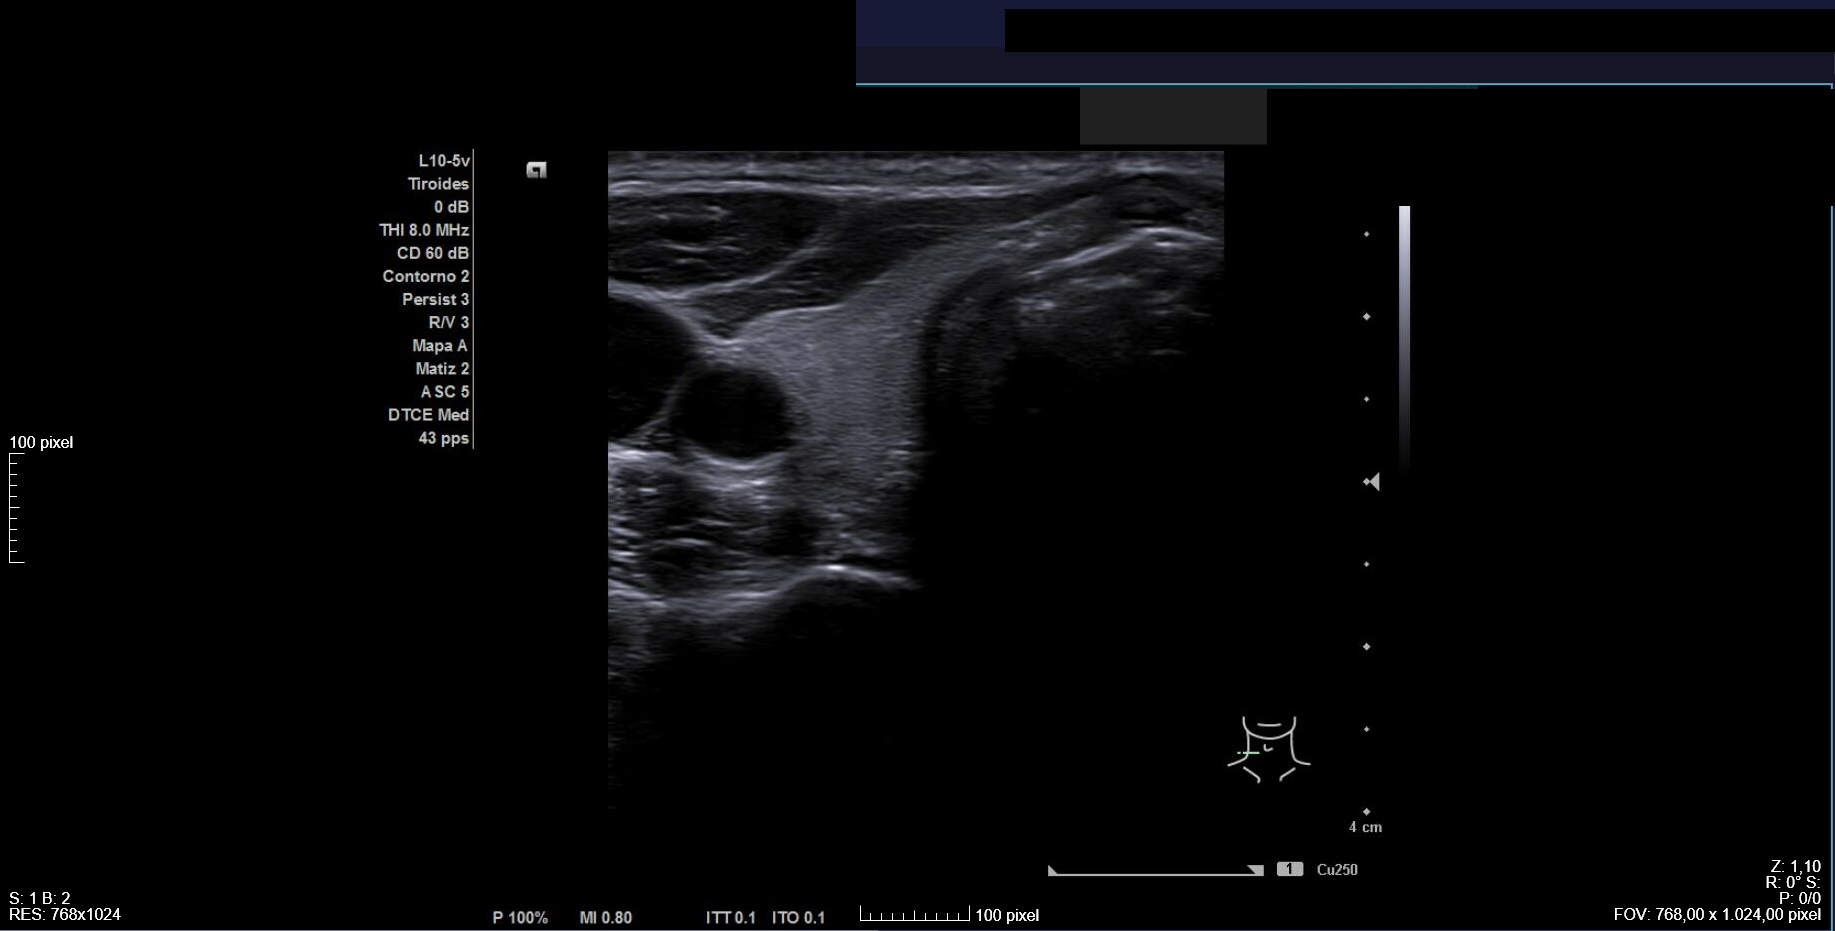

Citamos para seguimiento clínico-ecográfico dos meses después. El bulto había tenido una evolución fluctuante en tamaño pero habían reaparecido las molestias. Nueva ecografía (Imagen 4) confirmó nódulo de características similares a las iniciales, de tamaño ligeramente inferior (2,1 x 2,3 cm). Se observaban focos ecogénicos puntiformes y ecogenicidad indeterminada (TIRADS=4).